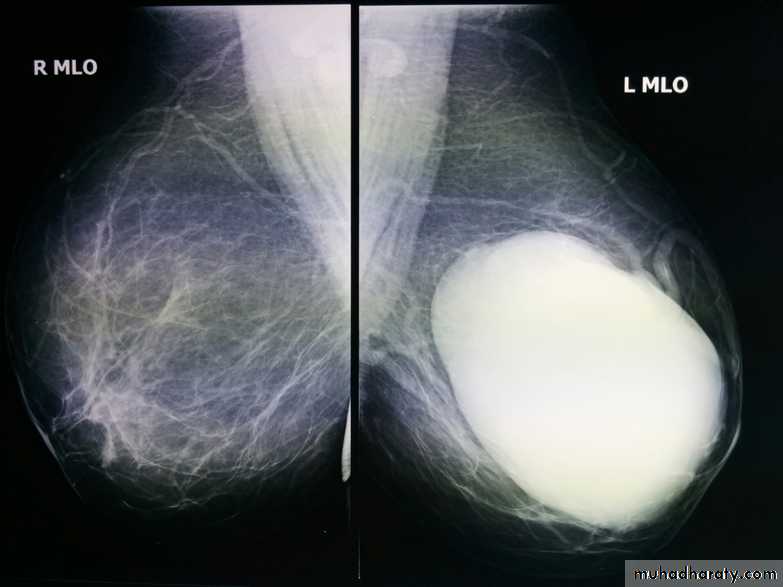

The mediolateral oblique (MLO) view is one of standard mammographic views. It is the most important projection as it allows to depict most breast tissue.